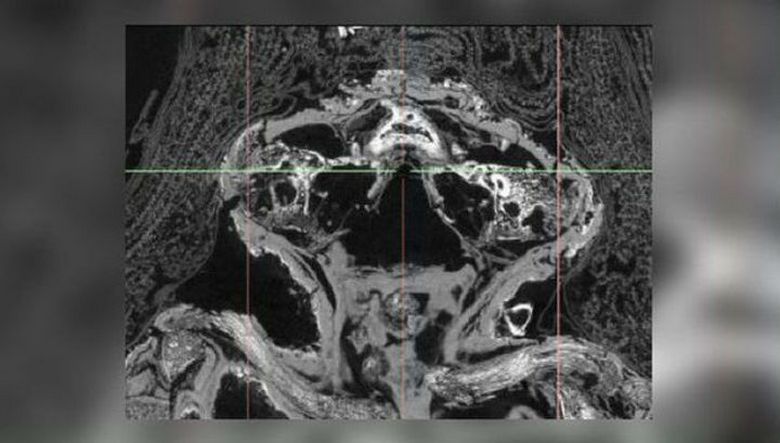

In prav pred kratkim je bila »mamica sokola« podvržena temeljitemu skeniranje (mikro-CT skeniranje omogoča znanstvenikom, da vidijo in pomeni in natančno preučite notranjo vsebino mumije, ne da bi jih odstranili in brez kršenja njenega pogrebnega gradiva) skupaj z drugimi muzeji eksponati. Kar je presenetilo raziskovalce, ko so ugotovil, da ti ostanki ne pripadajo ptici, ampak mrtvorojen nedonošenček.

Izkazalo se je, da ta otrok še vedno trpi v maternici tako redka bolezen kot anencefalija, pri kateri se ne razvijejo možgane in sam lobanji, kar je povzročilo splav. Otrok je bil star približno 25 tednov, že se je oblikoval telo, okončine, celo prste na rokah in rokah, vendar zgornji del lobanje – ne. Poleg tega je trpel tudi zaradi prirojene razcepne ustnice – torej imenovano razcepno nepce. Presenetljiva je še ena stvar: iz katerega razloga je to splav je bil mumificiran? Običajno so takšni “otroci” v starem Egiptu (in ne samo v njem) pravkar pokopan v lončkih in samo v najbolj redki primeri so se zgodili točno tako, kot vidimo – mumificiran. Očitno je otrok veljal za posebnega in njegovega mrtvorojenost – vreden odhod v svet mrtvih …